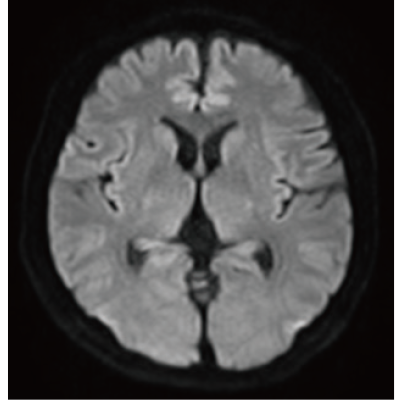

IP-RAPID x DLR Plus can be used for basic imaging such as VolumeScan, RadialScan, HalfScan, and many other imaging methods such as MultiContrastScan FatSep and DWI.

It can also be used with time-consuming scans such as Whole Body DWI and Whole Spine imaging, providing more detailed information in many areas than previously possible.

Deep Learning technology*8 enables image quality adjustment after imaging is complete. It optimize SNR and improve image sharpness by processing MRI signals in stages (k-space signal processing).

This brings super-resolution and reduces truncation artifacts.